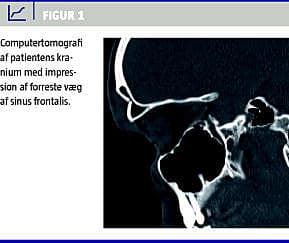

På mistanke om fraktur af sinus frontalis blev der af logistiske årsager i første omgang taget et røntgenbillede af kraniet i to planer. Billedet viste impressionsfraktur af den anteriore væg af højre sinus frontalis med en diastase på 1 cm. En efterfølgende computertomografi af kraniet viste, at det løsslåede parti af den anteriore væg lænede sig op ad den posteriore væg, som var intakt (Figur 1 ). Der var ingen intracerebrale skader, og knoglestrukturen i kraniet var normal.